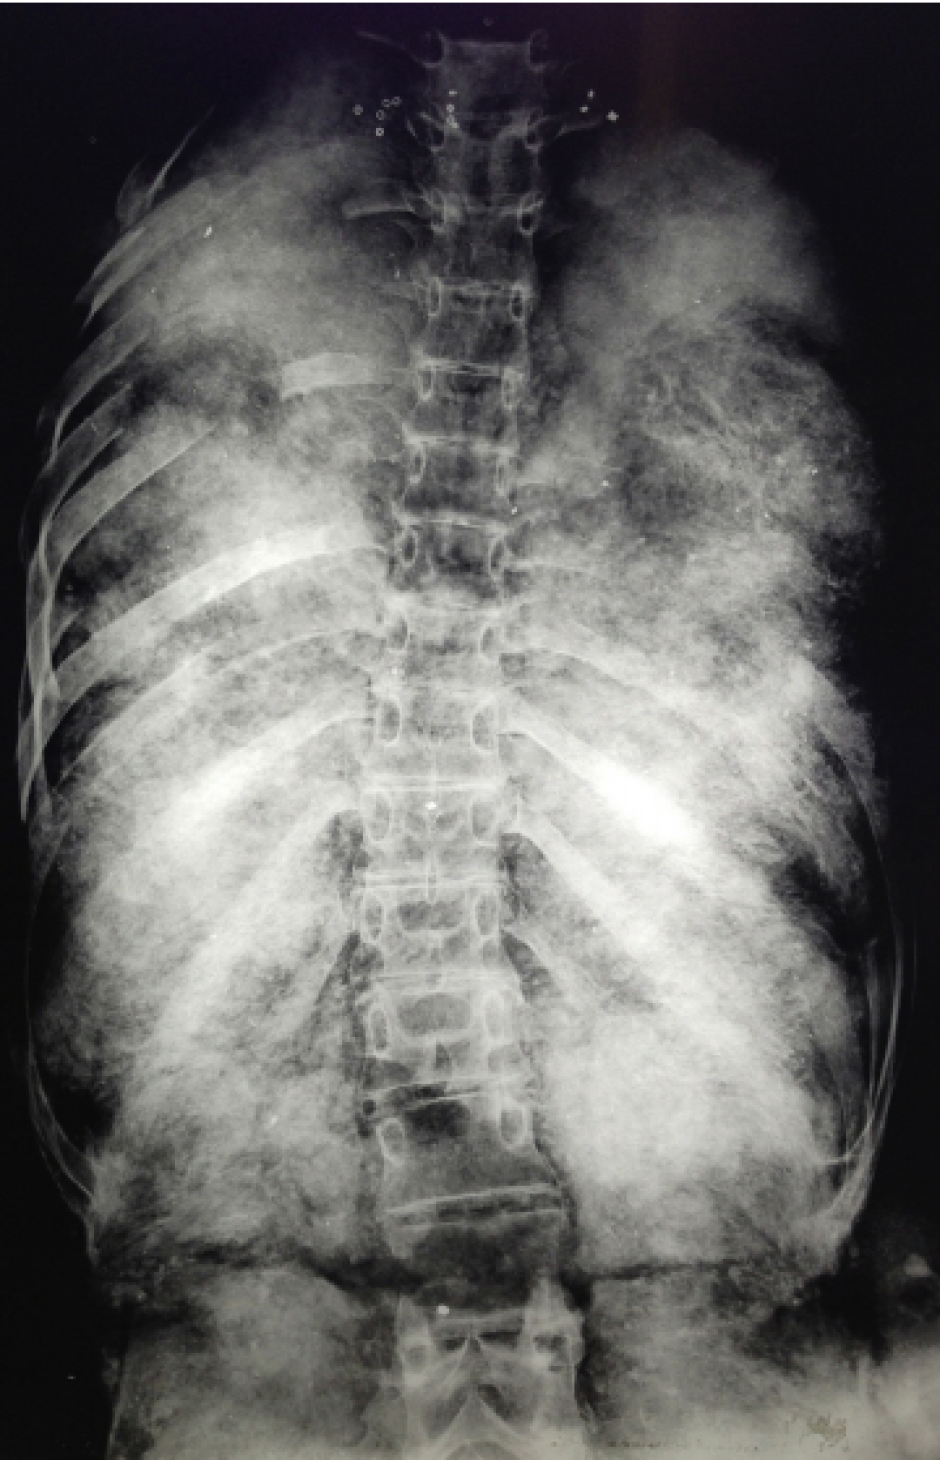

Radiografía del torso de Tutankamón que muestra el estado de las costillas, así como el relleno de la zona abdominal.

Radiografía del torso de Tutankamón que muestra el estado de las costillas, así como el relleno de la zona abdominal.R. Connolly / ResearchGate